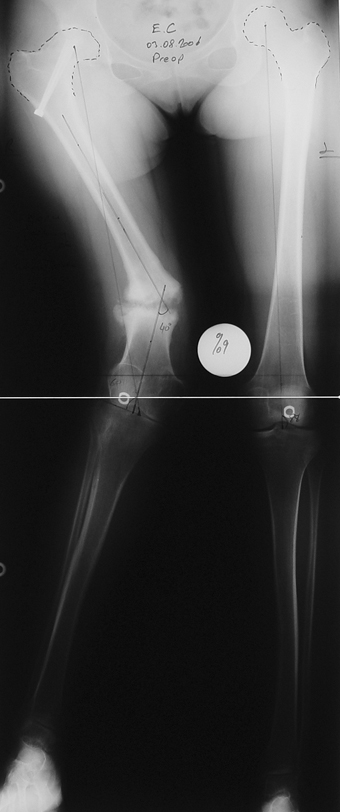

Travma Sonrası Bacak

Vaka 4